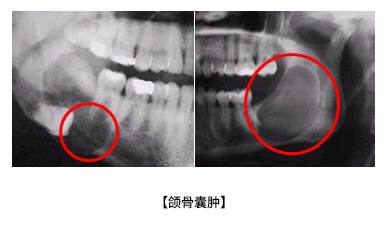

頜骨囊腫